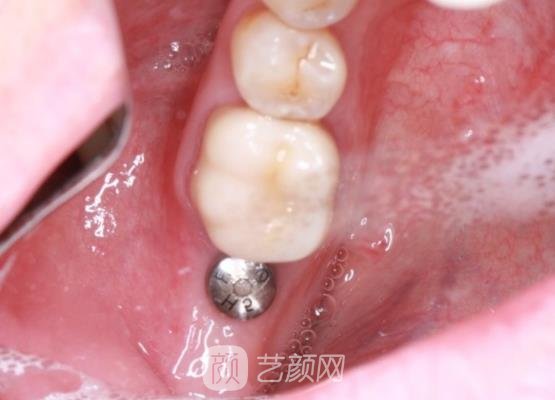

来到这个科室以后,这里的口腔医生为我做了全方面的检查,并且还问了我个人的一些想法,还给我看了一下口腔里边的具体情况,在都准备好了之后,接下来就要开始进行手术了,其实做手术之前我并没有太大的把握,怕一旦做不好的话,可能会给口腔带来一些伤害。

不过在接下来的几个小时里,我还是很配合医生的,按照医生交给我的每一步细心的操作,所以整个手术下来还是比较轻松,也没有用了多长时间,在完成手术之后,我按照医生的交代,做好术后的每一步护理工作,所以现在我的牙齿修复的良好,我很满意。